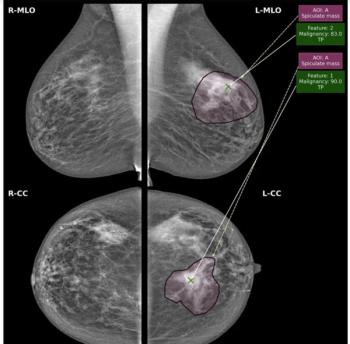

While there was a decline of AUC for mammography AI software from breast-level assessments to lesion-level evaluation, the authors of a new study, involving 1,200 women, found that AI offered over a seven percent higher AUC for lesion-level interpretation in comparison to unassisted expert readers.